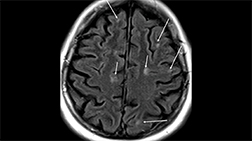

Typical lesions of multiple sclerosis are found in the infratentorial regions.

Inferior temporal lobe lesion. An inverted J lesion is in the left inferior temporal lobe, and a subtler lesion is in the right temporal lobe. Note the peripheral brainstem lesion in the left midbrain and a lesion in the left temporal cortex.